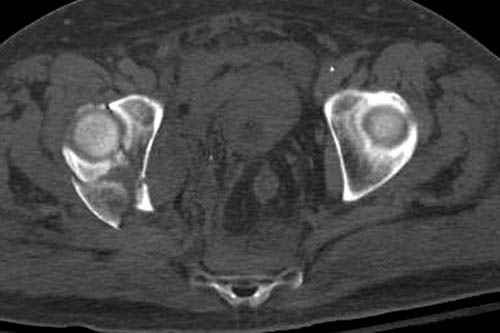

По возможности вышлите снимки, сканы таза до

реконструкции, интраоперационные.

По снимку создается впечатление о высоком поперечном переломе, задней колонны, стенки; почему не пользовались *magic screw*?

Снимки здесь....